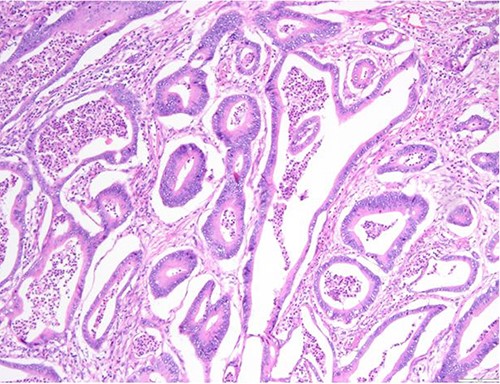

The definitive pathological report revealed adenocarcinoma metastases with morphology and immunophenotype compatible with an intestinal origin, both in splenic parenchyma and in uterine myometrium (see Figs 1–8).

Surgical specimen: hysterectomy; macroscopically, an intramural nodular, yellowish, well-circumscribed neoplastic lesion, 45 mm in diameter, collapsing the endometrial cavity is seen.

Surgical specimen: hysterectomy; microscopy, HE; endometrium and myometrium infiltrated by well-formed neoplastic glandular structures composed of cells with ‘pencillated’ and atypical nuclei, with nucleoli, apoptosis and mitotic figures, consistent with an intestinal origin (metastatic colorectal adenocarcinoma).

Surgical specimen: hysterectomy; microscopy, HE; endometrium and myometrium infiltrated by metastatic colorectal adenocarcinoma.